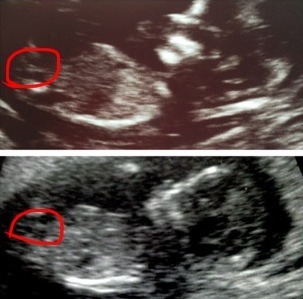

Ok -so I can't stop staring at my 12 wk, 5 day scan. I have asked ynwa if I can use one of her pics to compare to mine (hers is confirmed girl). Ynwa's little one is on top and mine is on the bottom. I'm posting them regular and then also posting one where the nubs are circled. Please help my craziness LOL! My gender scan is on Dec 1st!!!!

Attachment 6387